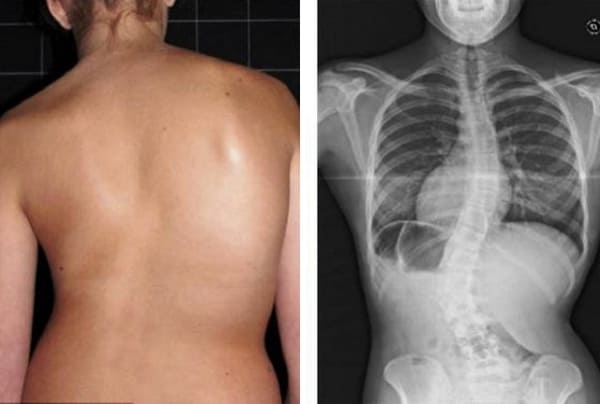

Mire esta radiografía. Es la columna de una persona de 44 años, pero parece la de un anciano. Antes, este tipo de daño aparecía después de los 60 años y, hoy, es muy común en personas de poco más de 40. Estos cambios progresan con la edad, y ignorarlos amenaza con una pérdida completa de movilidad.

Columna de un paciente de 44 años: todo comenzó con un dolor simple, pero en una semana apareció la hernia, y en dos semanas — desplazamiento de las vértebras, compresión de nervios y silla de ruedas.

Mire estas fotografías. Esto es lo que les sucedió a todos los que ignoraron los síntomas. Hoy, estas personas están completamente sin esperanza, y muchos de ellos no tienen a quién acudir en busca de ayuda. ¿Realmente, quiere un destino así?

Mujer de 52 años. Desplazamiento y deformación severa del disco intervertebral, compresión de los nervios y daño a la médula espinal.